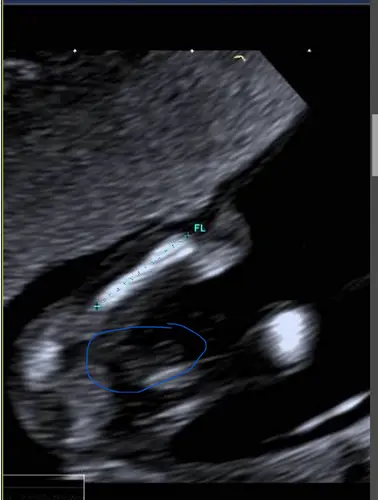

Betreft het uitsteeksel heeft ze gelijk. Ook bij meisjes steeks het wat uit, alleen is er dan een driedeling te zien (bij jou ook), dus wit, donkerder, wit. Een “hamburgertje”😍 gefeliciteerd!!

Het kan ook de navelstreng zijn wat uitsteekt en het dus toch meisje is. Ik durf het niet te zeggen bij je

Oooh echt. Ik was bijna zeker van mn zaak😂 gezien je ook aan het einde van het geslacht/uitstulping 3 streepjes ziet wat lijkt op de urinebuis. Maar weet niet of dat uberhaupt al zichtbaar kan zijn met 13 weken..

Wat jij ziet is idd de navelstreng. Zo groot is het nog niet haha. Ik ben nu in verwachting van mijn 2e zoontje en heb nog een dochtertje maar op de echo ziet een piemeltje er wel anders uit haha!! Kan zijn dat je natuurlijk wel een jongentje krijgt maar dit is niet zijn geslachtsdeel 🤪 Dit is de echofoto van de geslachtsecho van deze zwangerschap en zo zag het er bij mijn andere zoontje ook uit. Vind het een beetje lijken op een champignon haha

Het “grote” wat jij ziet is echt de navelstreng, als je er naast kijkt zie wel wat en zou kunnen duiden op een piemeltje maar daarvoor is de echo niet heel scherp voor om echt goed te beoordelen.